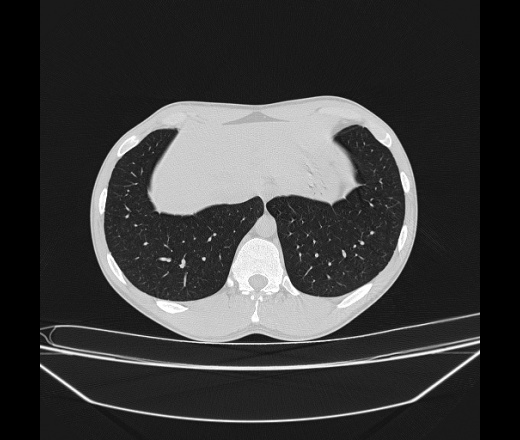

Молодой парень 18 лет, призывник, при прохождении ФЛС на верхушек левого легкого выявили очаги средней интснисвности с нечеткими контурами, тяжи. Сделали бок и томограммы 6-7-8. Везде описывают как очаговый твс. Вижу только перибронхиальный фиброз. Что за изменения в бронхах, указано нижи стрелками, тоже перибронхиальный?